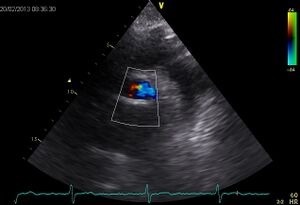

| Plax by tilted (Plax PV) | PSax Ao |

| Suprasternal apd (color doppler) | Dilated apd (Plax PV) |